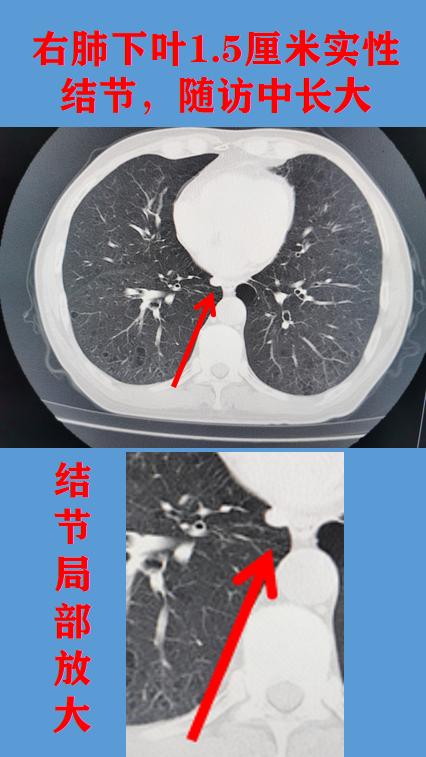

胸部CT提示淋巴结,手术病检小细胞肺癌。周二出肺癌肺结节门诊,来了一位男性患者,59岁,机关工作人员。自述发现右侧胸腔结节3个月,近日复查长大,原来1.3厘米,现在1.5厘米。

我看了它的胸部CT图片,该患者有2个肺实性结节,一个位于右肺上叶前段,一个结节位于右下肺,靠近食管。右下肺结节胸部CT报告提示:食管旁淋巴结可能。

我仔细分析了患者的片子,患者结节短期内长大,生长迅速,虽然表面光滑,但良性肿瘤一般不会生长如此快,如是淋巴结,患者一年前体检应该就有,但追查一年前片子,并未见该结节。综合判断,恶